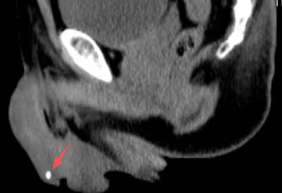

“当时就感觉钻心地疼,有出血,连尿尿都不顺畅。”回忆起事发时的情况,51岁工人卫大叔(化名)仍心有余悸。原来,他在工地切割钢管时,一粒飞溅出去的芝麻大铁屑,竟不偏不倚射入“丁丁”头部。在历经9小时、辗转两家医院后,卫大叔最终在ky通过手术成功取出这枚铁屑。 图:从患者“丁丁”头内取出的铁屑 意外突袭:芝麻大铁屑穿透衣裤,精准射入敏感部位 结合卫大叔的描述、临床症状及影像学检查,接诊医生大概还原了意外过程:他在切割钢管时,一枚飞溅出来的铁屑穿透工服、长裤和内裤,不偏不倚地正中“丁丁”头部。 从业数十年的老医生都感叹,“一粒小小的铁屑,居然像子弹一样能连续穿透3层衣裤,且不偏不倚射入敏感部位,这确实比较罕见”。 影像检查中可见患者“丁丁”组织内的金属异物 就医受阻:铁屑深埋海绵体,辗转就医仅做应急处理 由于铁屑嵌于阴茎海绵体内,该组织血运丰富、结构精细,钳取异物操作不太容易,当天正好是周末,大叔先后辗转两家医院,都仅进行了止血和抗感染处理,未尝试取出异物。此时距离意外发生已过去近9小时,由于铁屑嵌入“丁丁”内,他总感觉隐痛不适,还是希望能早点取出。 医生手术中 精准施救:5毫米小切口定位取铁屑 为求进一步治疗,经人介绍,卫大叔来到ky泌尿外科寻求治疗。经影像学检查可清晰地看到一枚铁屑嵌在患者龟头里面,泌尿外科主任蒋勇军分析认为,虽然该区域血管密集,但是准确定位、小心处理,还是可以取出来的。 手术时,蒋勇军主任发现患者“丁丁”处伤口已闭口,仅可见一小红点,于是沿小红点纵向切开约5毫米,小心探查至海绵体组织约5毫米深处,顺利找到铁屑并钳出,由于伤口极小,术后第二天卫大叔就顺利出院了。 人体组织内遗留异物是否需要取出,取决于异物的类型、位置、大小、是否引发症状及潜在风险等问题,不能一概而论。 蒋勇军主任指出,为避免继发感染、疼痛不适等问题,人体组织内最好尽量取出,但细小的金属异物在疏松的组织内,往往比较难找到或取出,让其存留在组织内也可能影响不大。然而在这个病例中,异物在“丁丁”头部这种敏感部位,还是建议取出为好。